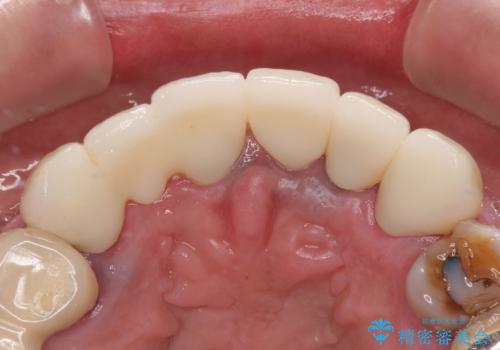

- 治療中の医院で装着した仮歯が汚れていて恥ずかしいとのことで来院された患者様です。

仮歯が不適合で歯肉が腫脹していたため、しっかりと調整した新しい仮歯にして腫れを改善した上で、オールセラミッククラウンにて補綴することとしました。

仮歯の隣の歯も詰め物の範囲が広く、仮歯をセラミックに置き換えても統一感のない口元となってしまうため、相談の結果、前歯6本をオールセラミッククラウンにて補綴治療を行うこととしました。

仮歯での期間が長かったとのことでしたが、当院での治療開始後はあっという間に綺麗な前歯に仕上がり、患者様には大変満足していただけました。